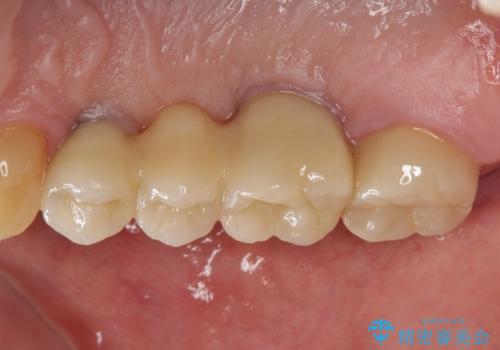

インプラント治療・セラミック治療を含む 全顎的虫歯治療

以上のような問題を、徹底的な虫歯治療、歯周外科、インプラント治療、部分矯正治療、精密根管治療を用いてひとつずつ解決ししっかりと長期的に食事を楽しめるような口腔内環境の再構築を目指します。

セラミック治療の注意事項(リスク・副作用など)

- 天然歯を削ります

- 硬い素材は天然歯を傷つけてしまう場合があります

- かみ合わせや歯ぎしりが強すぎる方はセラミックが割れてしまう可能性があります

- 自費診療(保険適用外治療)となります